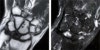

초기에는 월상골이 주위 손목뼈에 비해서 희어 음영이 증가되어 보이고, 진행되명 뼈의 괴사로 인하여 조각이 나고 붕괴가 되며, 결국에는 손목관절의 관절염 소견이 나타납니다.

무혈성 괴사 초기에는 방사선 골 주사나 MRI가 도움이 될 수 있습니다.

MRI : 키엔벡 병(월상골의 무혈성괴사, Kienbock's disease)